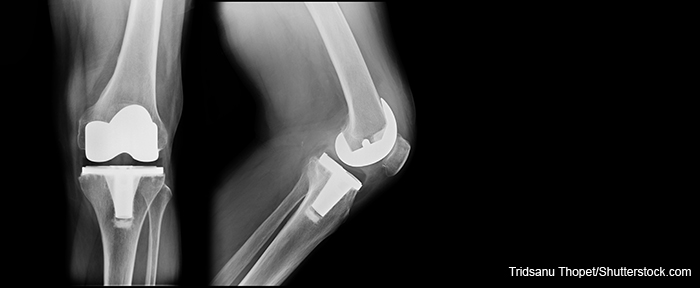

Twenty percent of the patients in the case series had filled at least one opioid prescription within three months prior to total knee arthroscopy (TKA). All eight of them required opioids during the three months following surgery. Although pain scores improved over time for all patients, patients who used opioids after TKA reported higher levels of pain at each evaluation time point compared with those who had an opioid-free TKA.The authors write that prolonged opioid use after TKA is associated with higher rates of infection, stiffness, and aseptic revision. As well, excessive prescribing of opioids after TKA increases the risks for misuse, abuse, dependence and overdose, and contributes to the national opioid crisis. This pilot study was intended to demonstrate that opioid-free TKA was possible; however, results indicate that the majority of patients who used opioids during the three months prior to TKA required opioids to control pain following TKA. How to mitigate prolonged opioid use after TKA for this highest risk subgroup remains an area ripe for investigation.

The authors conclude that “although there is no consensus about the optimal multimodal pain protocol for use in TKA, a growing body of evidence indicates that modalities that target a variety of pain pathways can produce additive or synergistic benefits. Future research should seek to determine which elements of the protocol are most essential for effectively managing pain and minimizing opioid use after TKA and investigate novel approaches to achieving opioid-free status in TKA patients who receive preoperative opioids.”“Achieving enhanced recoveries after knee replacement surgery has been a long-standing challenge,” notes Dr. Dasa. “With recent innovations and improved surgical techniques, we are now able to achieve results many have found difficult.”